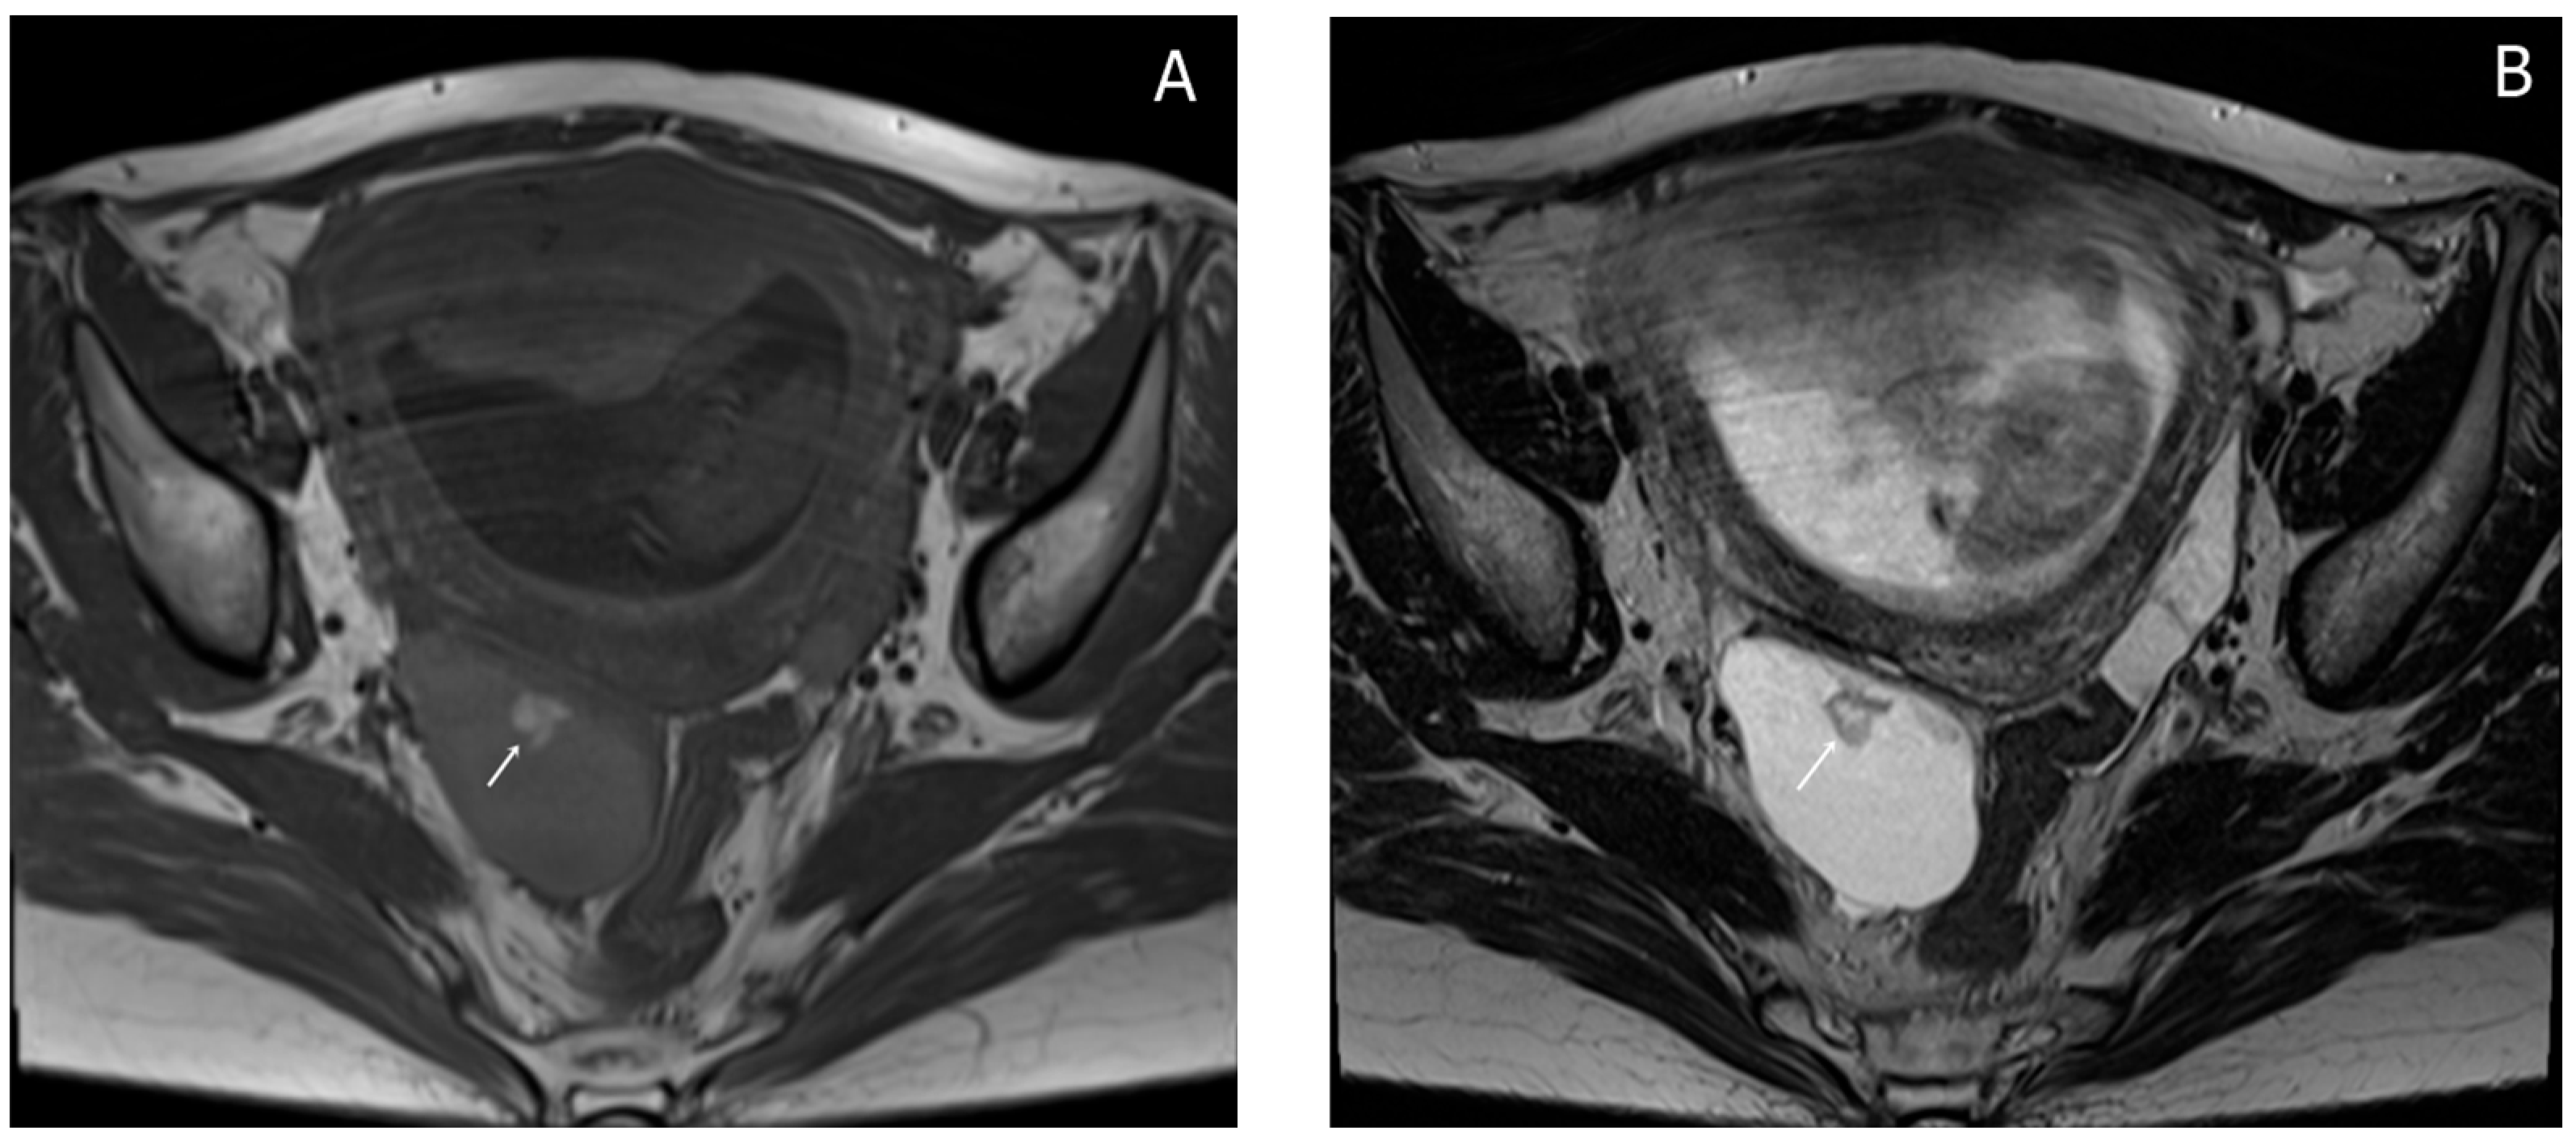

Almost a week later she performed a native MRI which highlighted: uterus with cranio-caudal dimensions of approximately 17 cm, no suspicious lesions at the level of the fetal content are visualized on the sequences performed; the left ovary measures approximately 37 mm in the anteroposterior plane; a space-replacing cystic process (ORADS4), located at the level of the right ovary, extended over an area of up to 56/45/60 mm (ap/ll/cc), reveals filiform septation of up to 2 mm in the right anterolateral quadrant, inhomogeneous solid inclusions with a thickness of up to 9 mm, approximately 3 papillary projections, intralesional hemorrhagic stigmata and a wall with a thickness of up to 3 mm; no space-replacing processes evident on MRI at the level of the rectal wall; no bone lesions with an oncological meaning evident in the examined MRI field; infracentimetric lymph nodes in the short axis located at the level of the internal and external iliac stations bilaterally (Figure 4, Figure 5 and Figure 6).

Figure 4. Sagittal TSE-T2WI images (A) and coronal TSE-T2WI (B) images show a thin smooth-walled unilocular cystic mass located behind the uterus, measuring (56 × 45 × 60 mm) with irregular soft tissue components (short arrow), papillary projections protruding into the lumen (long arrow) and incomplete internal septations (black arrow); there is a small amount of fluid around the lesion (dotted arrow).

Figure 5. Axial T1WI-TSE image (A) and axial T2WI-TSE image (B) show a unilocular right ovarian cystic mass. The signal intensity of the cystic component demonstrates intermediate signal on T1WI and high signal on T2WI. The intracystic papillary projection appears hyperintense on T1WI and hypointense on T2WI (arrows).